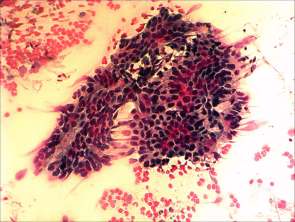

Cytological picture. There was no colloid in the background. Hyperchromatic epithelial columnar cells were found with clear cytoplasm. They were in irregular cell groups with loss of polarity and nuclear crowding.

Cytological diagnosis: a pattern corresponding to metastasis of the urinary bladder cancer.